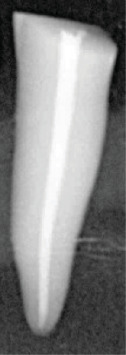

Abstract Image